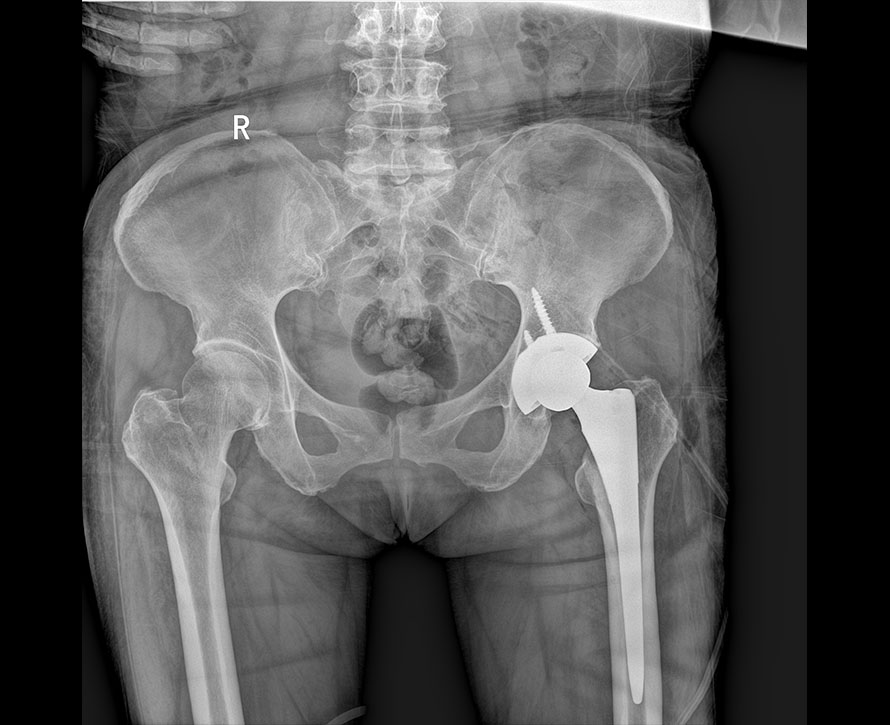

临床图像